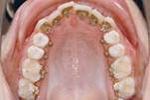

叢生150.jpg

→空隙歯列 (すきっ歯)→叢生

(でこぼこ、八重歯)